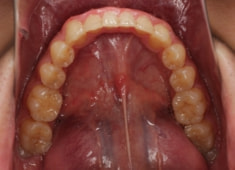

治療後(2年1ヶ月後)

大臼歯は整直されております。

歯根のパラレリングは良好です。

左上2番の歯根も問題なさそうです。

下顎8番は保定期間に入り、しばらくして咬合が安定してから抜歯する予定です。